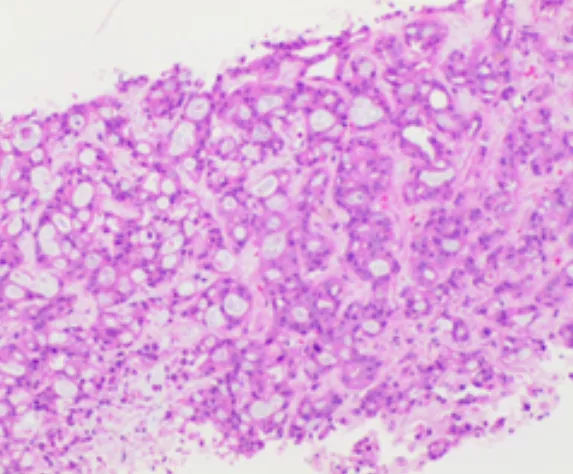

肝內(nèi)病灶穿刺組織病理結(jié)果

(肝內(nèi)病灶穿刺組織)肝組織內(nèi)見腺癌浸潤,免疫組化結(jié)果:CK7(+),CK19(+),Ki-67(約30%+),P53(彌漫強(qiáng)+),CEA(部分+),TTF-1(-),結(jié)合病史及影像學(xué)檢查,首先考慮胰腺癌轉(zhuǎn)移。